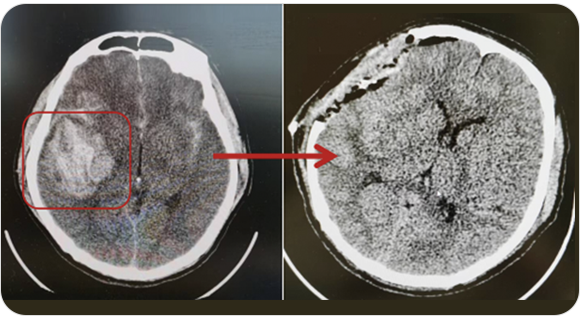

精通颅内动脉瘤介入栓塞和手术夹闭双技术,系统掌握脑动静脉畸形、颈内动脉海绵窦漏、硬脑膜动静脉漏等颅内血管疾病的诊疗和手术,精通颈动脉、椎动脉狭窄的血管内重建技术,以及颈动脉狭窄的内膜剥脱手术技术。在颅内肿瘤、椎管内肿瘤、颅脑损伤、高血压脑出血等疾病的诊治和手术,脑功能性疾病立体定向手术治疗等方面也积累了丰富的经验。

擅长脑血管病(出血与缺血)的神经介入与微创手术,能熟练开展脑外伤、重度颅脑损伤的救治工作。